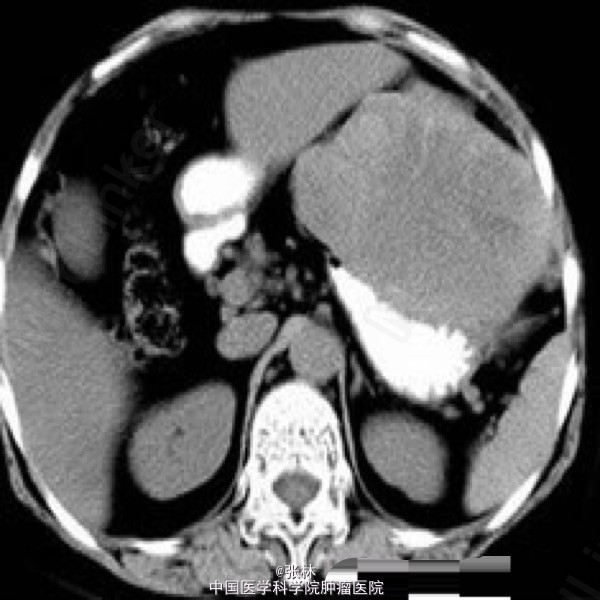

病史:女,65岁,上腹不适3年。

CT表现:胃体部前外侧壁可见一外生性肿物,体积大,形态较规则,边界清楚,肿物与邻近胃壁不可分,胃腔受压变扁;平扫呈较均匀等或略低密度,增强扫描明显不均匀强化,周边实性部分呈渐进性强化,中心可见片状无明显强化的更低密度区域。

术中:肿物位于胃前壁体底交界处,约12X10X10cm,占据上腹大部分,于肝左外侧叶稍粘连,肿物呈暗红色,质硬,肿物附近胃壁颜色、质地正常。 病理诊断:胃高度恶性间质瘤。